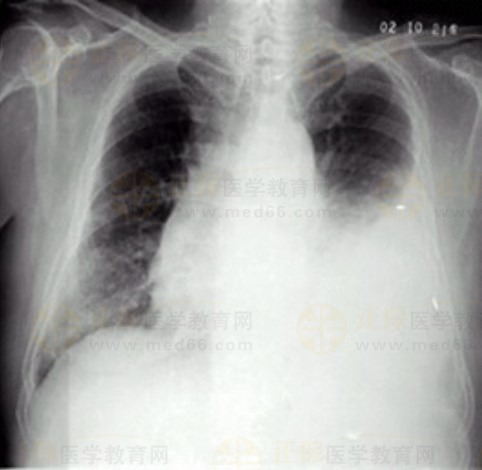

女性,55歲,胸悶、氣短5天,加重1天。診斷(X線-胸腔積液)如下,2023年臨床執(zhí)業(yè)醫(yī)師實踐技能考試在即,醫(yī)學(xué)教育網(wǎng)整理了技能2號考試卷影像診斷考題,具體如下:

02卷-5.女性,55歲,胸悶、氣短5天,加重1天。診斷

A.右上肺炎

B.左側(cè)胸腔積液

C.左下肺不張

D.左肺癌

本題答案:B

【該題針對“ X線-胸腔積液 ”知識點進(jìn)行考核】